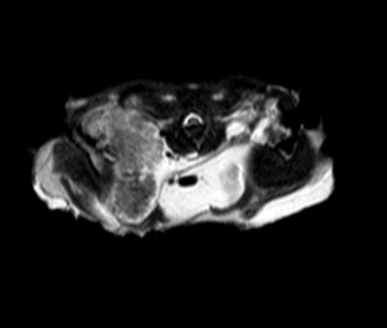

Результаты МРТ. В проекции поверхностной приводящей мышцы нижней челюсти справа, крыловидной мышцы справа, трапециевидной мышцы справа определяется объемное образование с линейными размерами 16×13×25 мм, без выраженных границ. Внутренняя сонная артерия интимно прилегает к медиальной стороне образования, которое вызывает сужение просвета ротоглотки, примыкая к правому гиоидному рожку подъязычной кости (фото 4, 5).

При внутривенном введении парамагнитного контрастного вещества – гадодиамид 0,15 ммоль/кг (омнискан 0,5 ммоль/мл, «ДжиИ Хелскеа Ирландия Лимитед», Ирландия) на отсроченных сериях определяется слабоинтенсивное накопление контраста выявленным образованием. В проекции наружной приводящей мышцы нижней челюсти справа определяется аналогичное по сигнальным характеристикам образование размером 5×4,5×3,7 мм (фото 6).